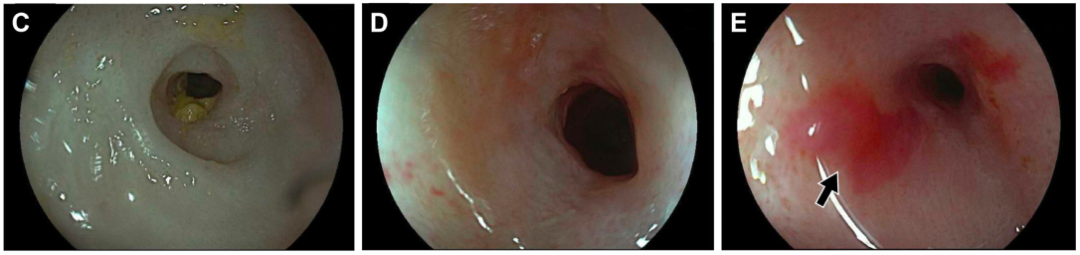

乙肝肝硬化患者合并肝门部胆管狭窄致梗阻性黄疸罕见病因1例

病史摘要:患者为 38 岁男性,因“发现乙肝 1 月余,腹痛 1 天”入院。1 月前诊断为“失代偿期肝硬化(脾大、腹水、门脉高压、食管静脉曲张)乙肝”,经抗 HBV、保肝治疗后症状缓解。入院前 1 天突发剑突下疼痛,进食后稍缓解,入院当日腹痛加重,伴恶心、呕吐。有吸烟及不规律饮酒史,现已戒酒,母亲因“肝硬化”去世,无慢性基础疾病、手术史、过敏史及有毒有害物质接触史。